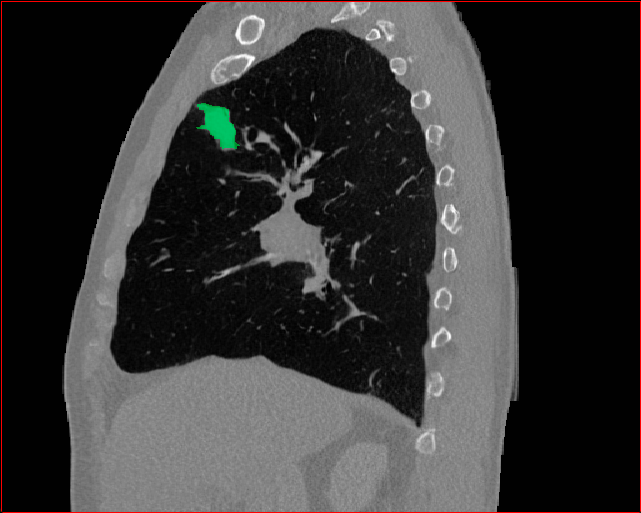

Figure 5 shows qualitative results for MAISI-v2 Controlnet on 5 types of tumors.

Lung Tumor

0.75×0.75×0.60.75\times 0.75\times 0.6

mm

512×512×512512\times 512\times 512

Figure 5: MAISI-v2 segmentation-guided results for five types of tumors. We show results for different voxel spacing and volume size to demonstrate the flexibility of MAISI-v2. Different Hounsfield Unit window is used to better show the contrast between tumor and normal tissues.